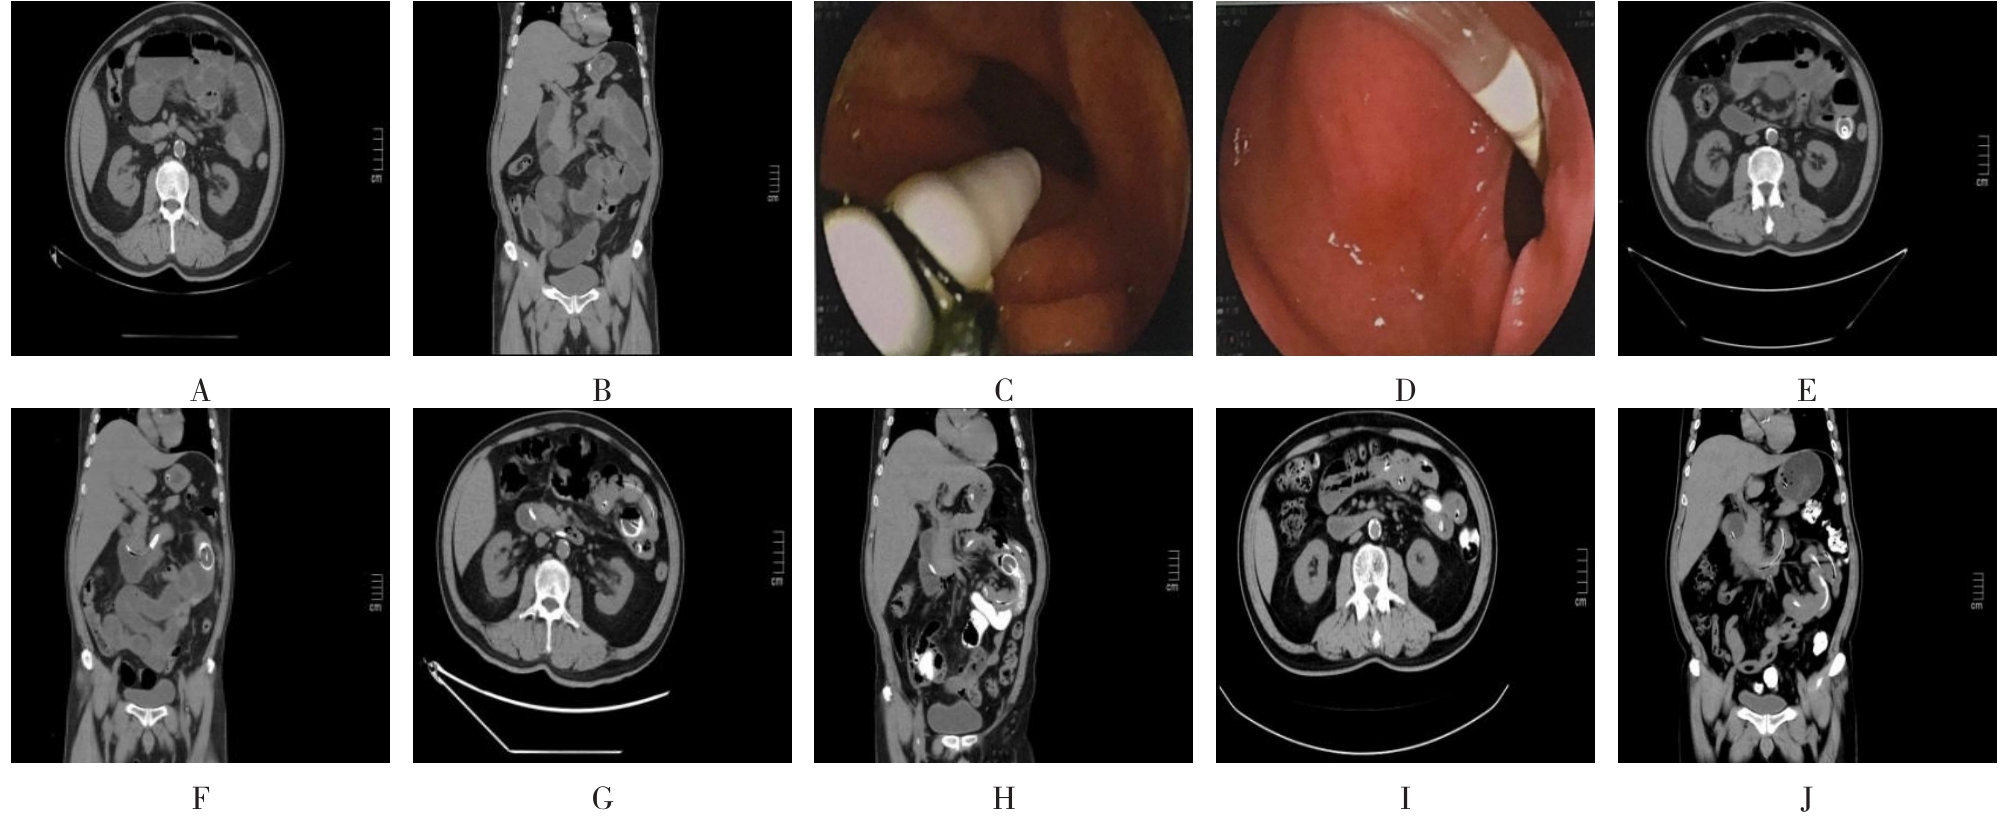

• 超声内镜引导下胃旁曲张静脉精准断流术治疗食管胃静脉曲张出血的疗效分析(附20例报告)

2025, 31(8):85-90. DOI: 10.12235/E20250036

摘要 (153) HTML (42) PDF 5.38 M (98) 评论 (0) 收藏

摘要:目的 探讨超声内镜引导下胃旁曲张静脉精准断流术治疗食管胃静脉曲张出血的疗效。方法 回顾性分析2024年1月1日-2024年12月31日于该院接受超声内镜引导下胃旁曲张静脉精准断流术治疗的20例肝硬化食管胃静脉曲张出血患者的临床资料,并评估治疗效果。结果 20例患者均顺利完成超声内镜引导下胃旁曲张静脉精准断流术;注射组织胶联合置入弹簧圈(16例)和单独注射组织胶(4例)均成功阻断胃旁来源的曲张静脉;所有患者均未发生穿孔、食管贲门狭窄、大出血、败血症和异位栓塞。1例单独注射组织胶的患者,术后胃旁曲张静脉少许渗血,经降低门静脉压力治疗3 d后好转,另1例单独注射组织胶患者,术后出现低热,抗感染3 d后体温恢复正常。结论 超声内镜引导下胃旁曲张静脉精准断流术治疗食管胃静脉曲张出血的临床疗效好,异位栓塞、大出血、感染和穿孔等并发症少,但仍需要密切随访,观察胃旁曲张静脉的排胶问题。